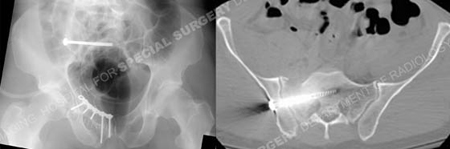

Postoperative anteroposterior pelvic radiograph and CT scan image illustrating acceptable reduction and placement of hardware.